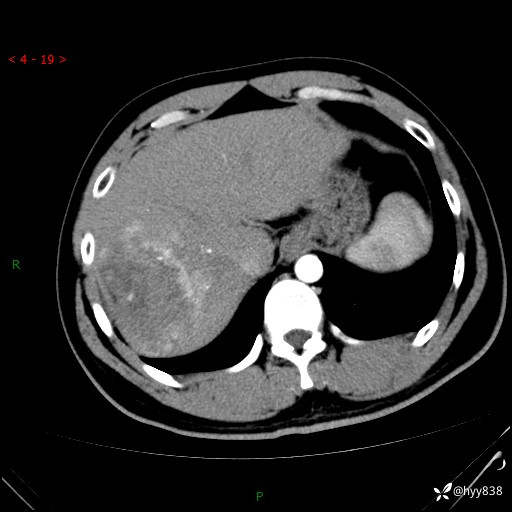

肝脏CT平扫

img